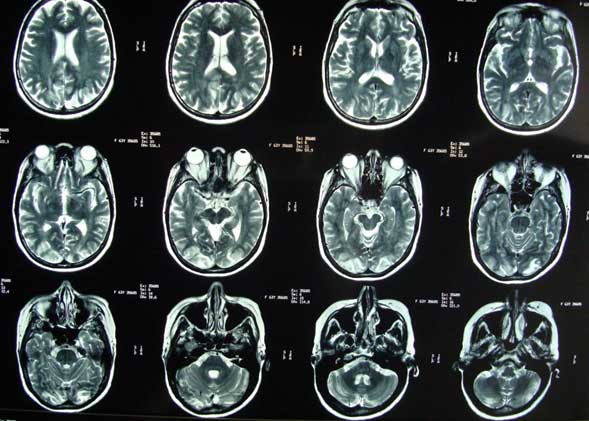

IRM T2 axial: Síndrome de Leucoencefalopatía posterior reversible (PRES) secundário a crisis hipertensiva por ergotismo (paciente con cefalea, crisis convulsivas y síndrome de Balint) (mismo caso).